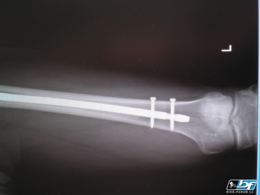

Druha noha po padu

IWY

4